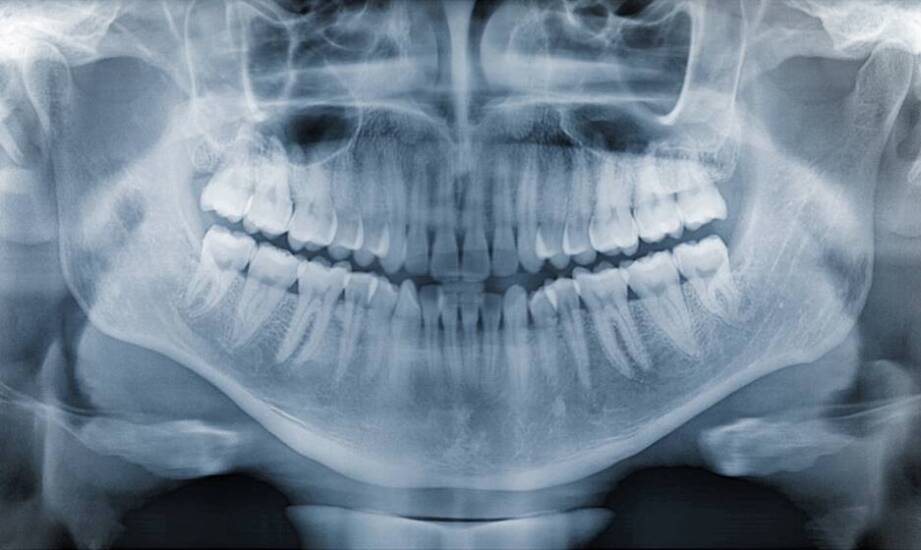

Stożkowa tomografia komputerowa (CBCT) to technika obrazowania, która znajduje zastosowanie w diagnostyce stomatologicznej. Pozwala na zobrazowanie struktur anatomicznych, co bywa potrzebne w planowaniu postępowania. Praktyka Dentystyczno-Implantologiczna Ewy Osękowskiej oferuje tę usługę, umożliwiając lekarzom ocenę problemów pacjentów oraz dobór postępowania do ich indywidualnych potrzeb. W artykule omówimy zastosowanie tej technologii zarówno dla pacjentów, jak i specjalistów, podkreślając jej znaczenie w stomatologii.

Jedną z cech stożkowej tomografii jest możliwość uzyskiwania trójwymiarowych obrazów, co wpływa na ocenę zmian w obrębie zębów i przyzębia. Dzięki temu specjaliści mogą ocenić stan pacjenta oraz zaplanować dalsze postępowanie. Praktyka Dentystyczno-Implantologiczna Ewy Osękowskiej zapewnia diagnostykę cyfrową, w tym tomografię stożkową (CBCT), która umożliwia obrazowanie struktur wewnętrznych zębów oraz otaczających tkanek. Badanie znajduje zastosowanie w różnych dziedzinach stomatologii, takich jak leczenie kanałowe, protetyka czy chirurgia stomatologiczna. Gabinet Ewy Osękowskiej oferuje świadczenia stomatologiczne oparte na diagnostyce, w tym obrazowaniu, w ramach opieki zdrowotnej w naszej dziedzinie.

Bezpieczeństwo pacjentów stanowi jeden z aspektów stomatologii, szczególnie w kontekście diagnostyki obrazowej. Stożkowa tomografia komputerowa (CBCT) jest jedną z metod obrazowania stosowanych w zależności od wskazań klinicznych. Technologie stosowane w diagnostyce obrazowej umożliwiają uzyskanie obrazów przydatnych diagnostycznie, co ma znaczenie m.in. u dzieci oraz osób wymagających powtarzanych badań. Warto zauważyć, że pierwsza wizyta dla najmłodszych powinna odbyć się przy pojawieniu się pierwszych zębów mlecznych, a dalsze kontrole będą zależały od zaleceń stomatologa oraz rodzaju leczenia. W przypadku potrzeby wykonania rtg zębów w Sopocie, Praktyka Dentystyczno Implantologiczna Ewy Osękowskiej oferuje pomoc stomatologiczną, z uwzględnieniem zasad bezpieczeństwa pacjentów w różnym wieku. Zakres badania oraz jego zasadność są ustalane indywidualnie przez lekarza, a wynik stanowi element dokumentacji medycznej. Stomatologia estetyczna, zachowawcza czy chirurgia to tylko niektóre dziedziny, w których może być wykorzystywana stożkowa tomografia komputerowa.

Stożkowa tomografia wspiera diagnostykę oraz chirurgię stomatologiczną, umożliwiając planowanie zabiegów. Obrazy pozwalają lekarzom ocenić anatomię pacjenta, co może być brane pod uwagę w implantacji. W przypadku leczenia implantologicznego CBCT pozwala na określenie lokalizacji oraz rodzaju implantu, a także ocenę jakości kości. W chirurgii stomatologicznej tomografia stożkowa znajduje zastosowanie przy usuwaniu zębów mądrości czy leczeniu guzów. Praktyka Dentystyczno-Implantologiczna Ewy Osękowskiej zapewnia wsparcie dla pacjentów w różnym wieku, dbając o zdrowie jamy ustnej oraz oferując świadczenia stomatologiczne w Sopocie.